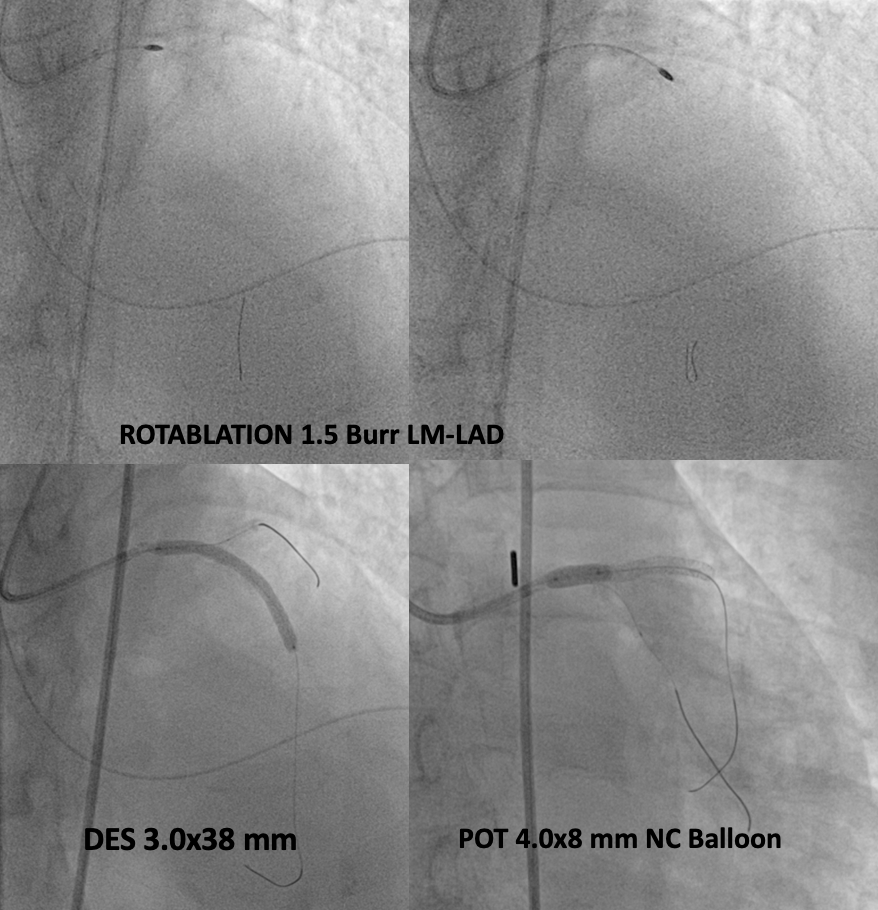

Percutaneous coronary intervention (PCI) of the LMCA-LAD lesion was performed with intra-aortic balloon pump (IABP) support. A 6 French EBU 3.5 guiding catheter was used to engage the left coronary artery. After wiring the lesion with a moderate support wire, intravascular ultrasound (IVUS) revealed an eruptive calcified nodule in the distal LMCA and heavy calcification (270-360 degrees) in the LAD. Rotablation was performed with a 1.5 mm burr for 3 runs. Following rotablation, the LAD wire was lost but successfully rewired. The LMCA-LAD lesion was predilated with a 3.0 x 15 mm non-compliant (NC) balloon. Provisional crossover stenting of the LMCA-LAD was performed with a 3.0 x 38 mm drug-eluting stent (DES). Proximal optimization was achieved with a 4.0 x 8 mm NC balloon inflated to 16 atmospheres (ATM) in the LMCA. The proximal-mid LAD was post-dilated with a 3.0 x 15 mm NC balloon inflated to 12 ATM. Repeat IVUS demonstrated good stent apposition and landing zones with no edge dissection, but the minimal stent area (MSA) in the proximal LAD required further optimization. Final post-dilation in proximal LAD with a 3.5 x 12 mm non-compliant (NC) balloon inflated to 16 ATM resulted in a good final angiographic result and IVUS-confirmed MSA of 8.01 mm2 in the LAD and 12.24 mm2 in the LMCA.